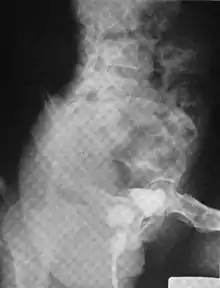

A urethral diverticulum seen on urethrogram

Urethral diverticulum is often an incidental finding.[2] It can be diagnosed using magnetic resonance imaging and/or micturating cystourethrography.[1] Other studies that can be used to diagnose urethral diverticulum include intravenous urography, urethroscopy, and/or ultrasound. Conditions that should be distinguished from urethral diverticulum in a differential diagnosis include overactive bladder, Gartner's duct cyst, Gartner's duct abscess, ectopic caeco-ureterocele, interstitial cystitis, pelvic inflammatory disease, endometriosis, and cancer.[3]